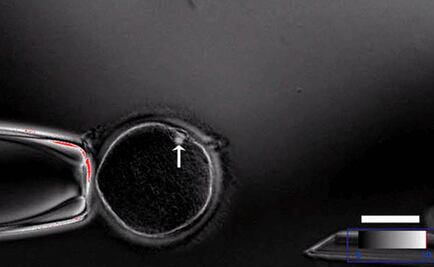

Cuatro de 26 embriones desarrollaron inmunidad, aunque el resto mostraron mutaciones "no planeadas"